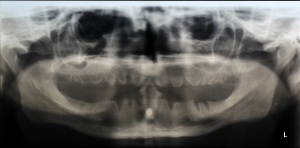

Diese Arbeit präsentiert erstmals eigene klinische und histopathologische Befunde zu Schleimhautveränderungen im Zusammenhang mit Snus-Konsum. Zudem werden dentale und parodontale Auswirkungen wie Zahnverfärbungen, Abrasionen, Karies, Gingivitis und Parodontitis beschrieben. Histologisch zeigte sich eine Entwicklung von reaktiver Gingivitis bis hin zu submuköser Fibrose, insbesondere an der bevorzugten Applikationsstelle im Vestibulum maxillare.